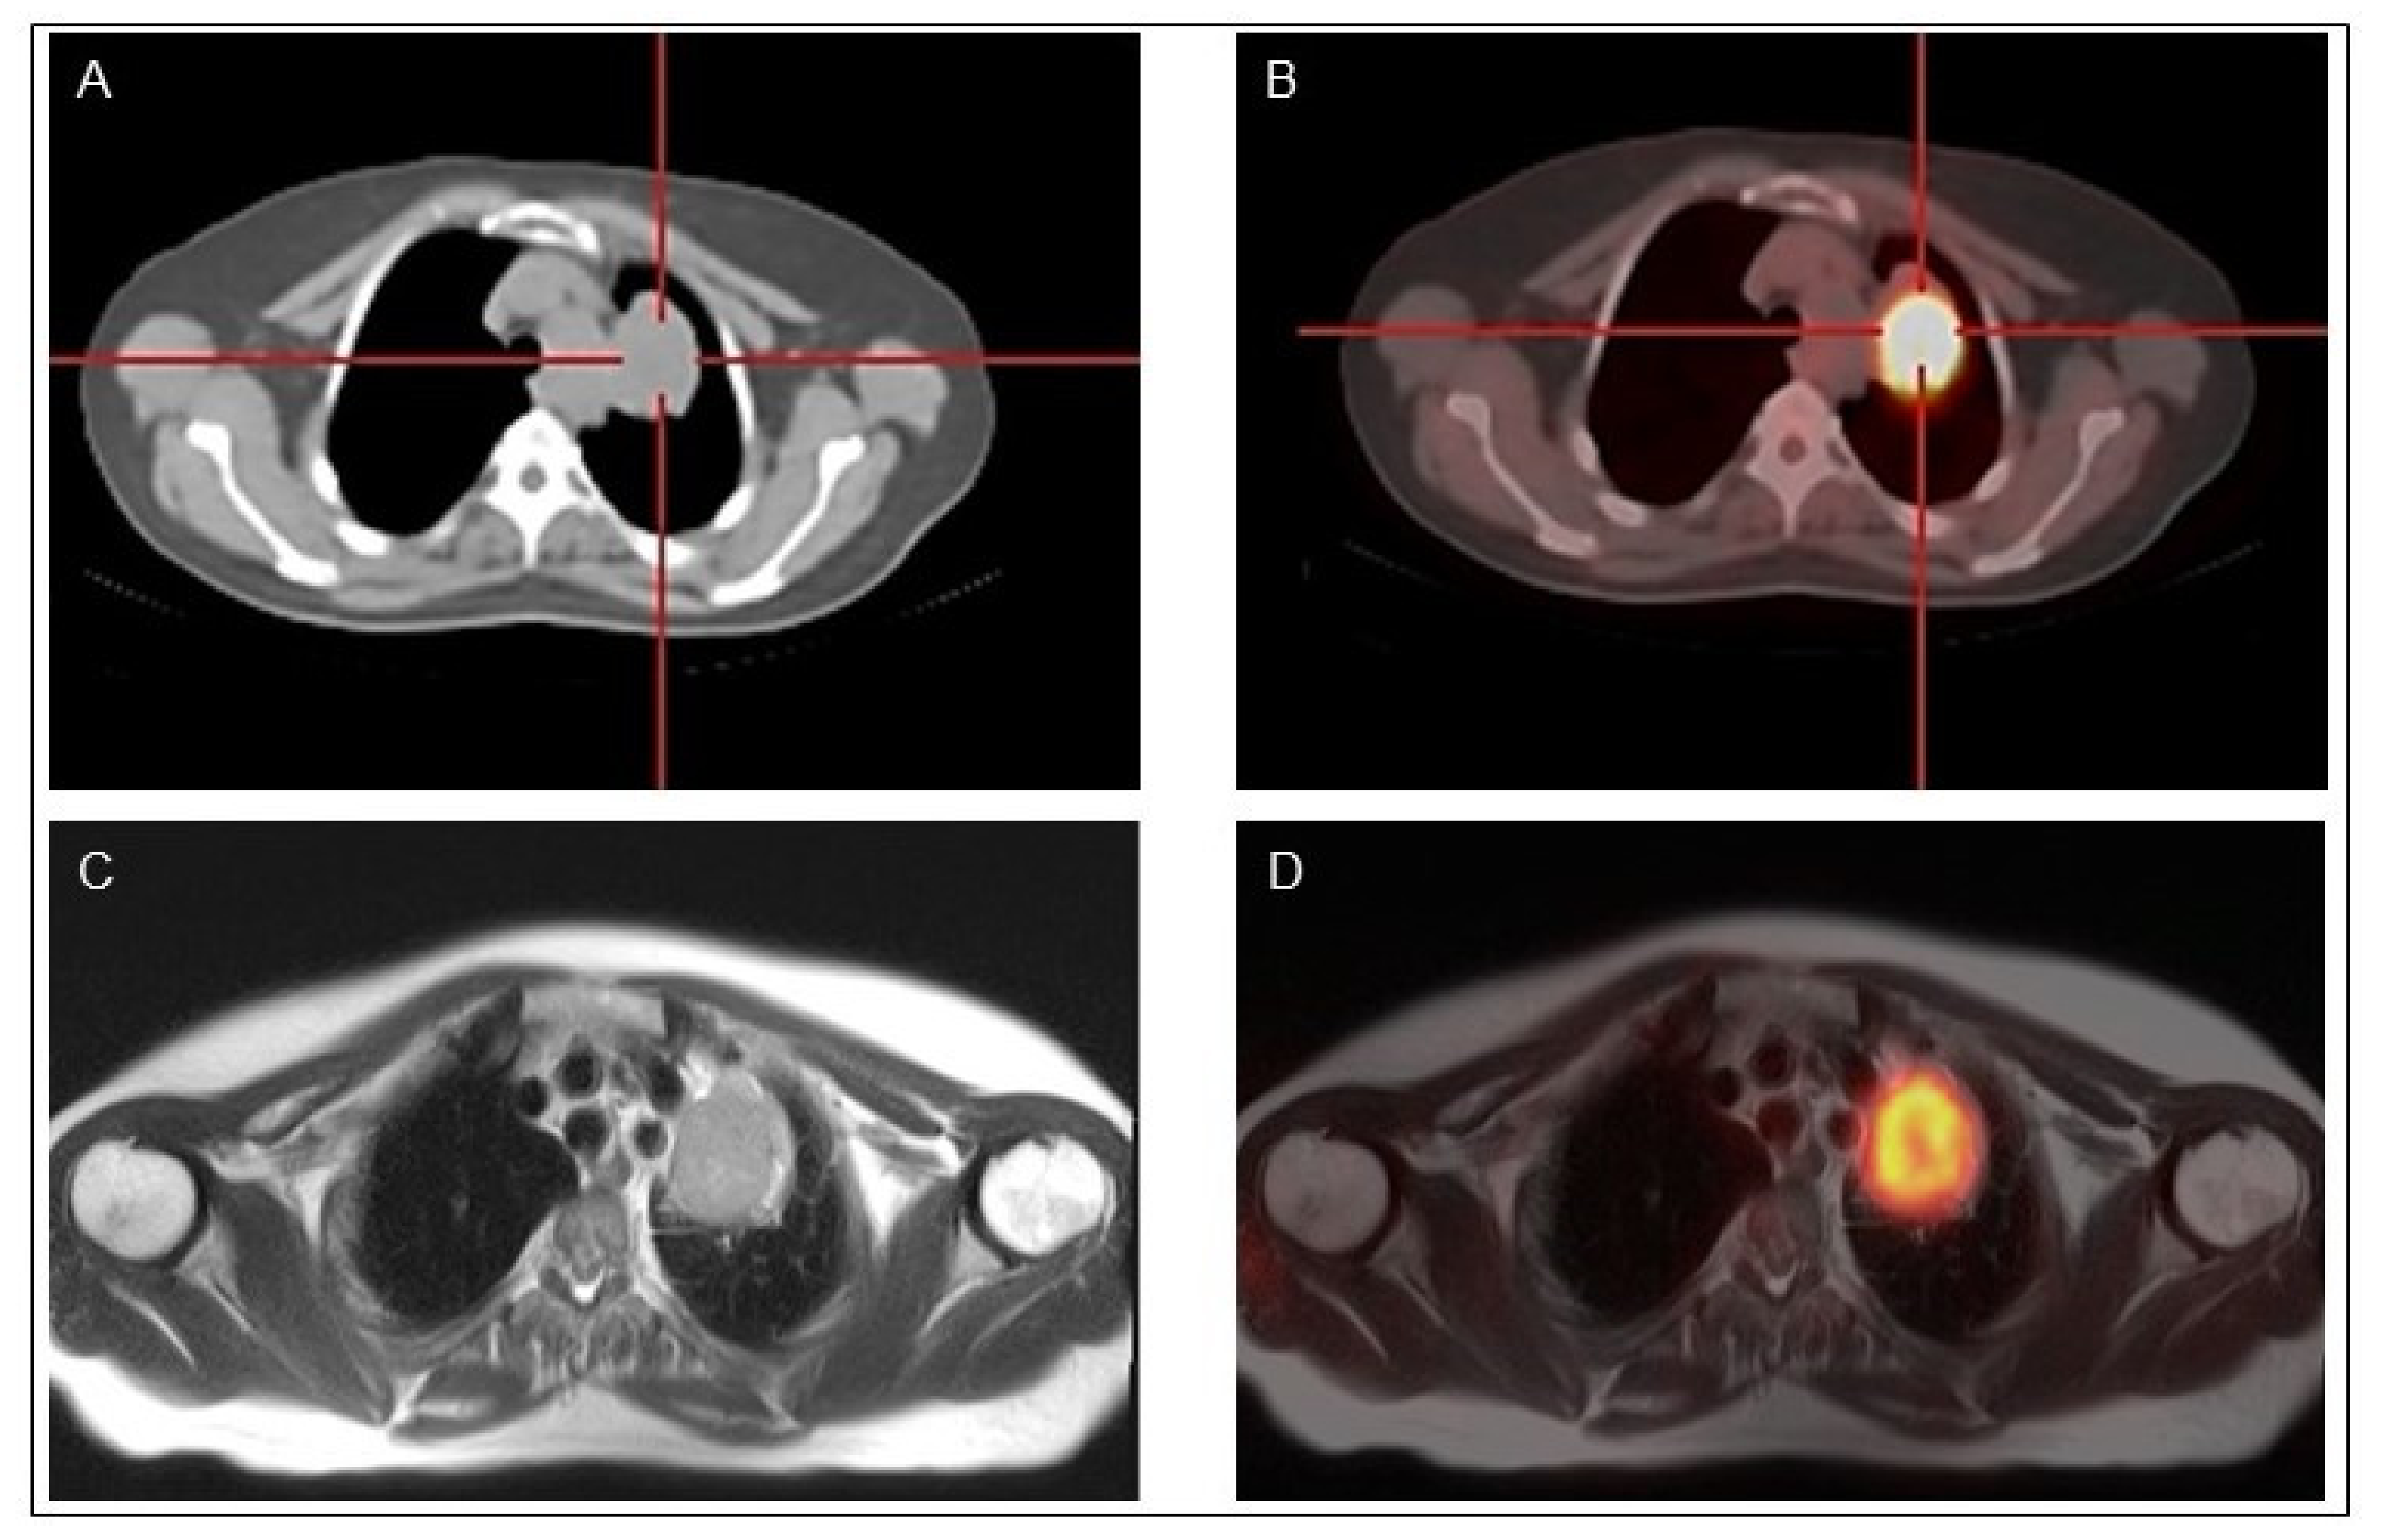

Indeed, PET/MR when available might be performed in selected patients with bone, soft tissue or liver lesions for whom a MR imaging is indicated (Figure 4).

Figure 4.

Classical papillary thyroid cancer in a 45-year-old man18F-FDG PET-CT (A,B) and 18F-FDG PET-MR (C,D) show a mediastinal lymph node with high 18F-FDG uptake.

Magnetic resonance (MR) imaging is a sensitive diagnostic technique for evaluation of DTC recurrence extent in the neck, mediastinum, bones, and liver. Simultaneous PET/MR provides complementary data. However, high costs and limited spread in diagnostic units limit its clinical routine use. Few studies on limited series of DTC patients found an excellent correlation between the two imaging techniques (PET/MR vs. PET/CT) despite, as expected, an inferior sensitivity of MR in the detection of lung metastases [88]. In a recent work, 40 consecutive DTC patients were evaluated at follow-up by sequential 18F-FDG PET/CT and 18F-FDG PET/MR imaging scans [89]. 18F-FDG PET/MR was positive in 11 patients detecting 33 lesions, while 10 patients showed positive findings with 30 lesions detected at 18F-FDG PET/CT.